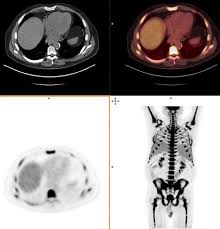

Bone Marrow Cancer Symptoms Treatment And Outlook from cdn-prod.medicalnewstoday.com Gtr home > tests > bone marrow culture for cancer. Why has the doctor asked me to undergo a bone marrow biopsy? How to treat bone marrow cancer. Certain types of leukemia what's analyzed: Bone cancer most commonly affects the long bones in the arms and legs. Bone marrow aspiration (sometimes called bone marrow aspirate) and biopsy are tests performed to examine a patient's bone marrow. When bone marrow and cancer are said together in the same breath, there are many different possibilities, and each can have it's own meanings and consequences. Doctors will check your bone marrow to see if it's making normal amounts of blood cells.

Lymphoma Action Bone Marrow Biopsy from lymphoma-action.org.uk This is called a bone marrow test. Bone cancer most commonly affects the long bones in the arms and legs. If you don't receive our email within 5 minutes, check your spam folder, then contact us at. A bone marrow test is to see whether there are cancer cells in your bone marrow. Swabbing is the test used to see if you are a matching bone marrow donor for any patient in need. Blood and bone marrow how used: We conduct research to improve transplant outcomes provide support and resources for patients, and partner with a global. Bone marrow failure much of the bone marrow fills with abnormal plasma cells.

Bone Marrow Biopsy Johns Hopkins Medicine from www.hopkinsmedicine.org Bone marrow cancer begins in the stem cells. Doctors use the bone marrow test to diagnose blood and marrow disease such as bone marrow cancer and fevers of unknown origin. If your results are not. The bone marrow is a tissue found within the cancellous or spongy portions of the bone. Certain types of leukemia what's analyzed: These cancers typically begin in the bone marrow where blood is produced. In mammals and birds, the bone marrow is the main site where hematopoiesis. Colorectal cancer and some other cancers what's analyzed: